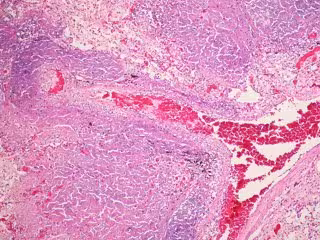

Tuberculosis

FLICKER/ PULMONARY PATHOLOGY